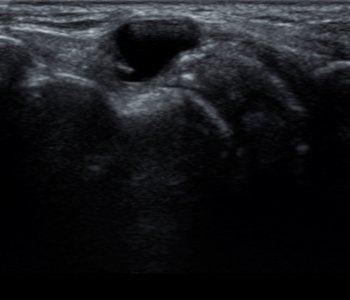

¹ß¸ñÀδëÆÄ¿

ÈçÈ÷ ¹ß¸ñÀ» »ß²ýÇß´Ù, Á¢Áú·¶´Ù

Ç¥ÇöÇÏ´Â

¹ß¸ñÀδëÁúȯ

Àδë´Â »À¿Í»À¸¦ ¿¬°áÇØÁִ ź¼º ÀÖ´Â Á¶Á÷À¸·Î, Çѹø ¼Õ»óÀ» ¹ÞÀ¸¸é ÀÚ¿¬ Ä¡À¯ µÇ´Â´ë ¿À·£½Ã°£ÀÌ °É¸®±â ¶§¹®¿¡ Á¶±â ¹ß°ßÇϰí Ä¡·á¸¦ Á¦¶§ ¹Þ´Â °ÍÀÌ Áß¿äÇÕ´Ï´Ù.

¹ß¸ñÀδëÆÄ¿ Áõ»ó

¹ß¸ñ°üÀý ºÎÀ§¸¦ ´·¶À» ¶§ ÅëÁõÀÌ ÀÖ´Ù.

Áõ»óÀÌ ¿À·¡µÈ °æ¿ì °üÀý¿¬°ñ ¼Õ»ó µî 2Â÷Àû ¼Õ»óÀÌ ³ªÅ¸³¯ ¼ö ÀÖ´Ù.

±Þ¼º¼Õ»ó½Ã ¹ß¸ñ°üÀý¿¡ ºÎÁ¾°ú ¿°¨À» µ¿¹ÝÇÏ´Â ÅëÁõÀÌ °ÇÏ°Ô ³ªÅ¸³´Ù.

¸¸¼º¼Õ»óÀÌ ±â´ÉÀûÀ¸·Î ¾àÇØÁö°í ¶Ù°Å³ª Á¡ÇÁ ½Ã ºÒ¾ÈÁ¤¼ºÀÌ ³ªÅ¸³´Ù.